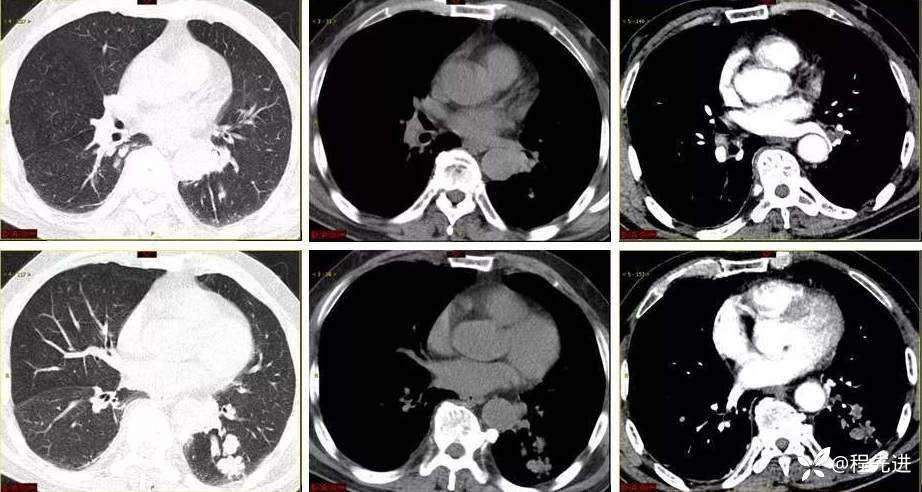

9月特别精彩病例|咳嗽伴咯血4月余,重点讨论胸部|结果已公布

患者性别:男

患者年龄:65岁

主诉:咳嗽伴咯血4月余

现病史:患者4月余前劳动后出现咳嗽,为阵发性干咳,以中午为主,后出现咯血,呈鲜红色,共5-6次,量最多时约50ml,约有3-4次。外院予以对症治疗(具体不详)后好转,1周前患者又出现咯血一次,约10ml。患者病程中无发热,时有胸闷,无胸痛,无呼吸困难,无盗汗,无恶心呕吐,无呕血黑便,食欲睡眠可,二便正常,体重无明显下降

有吸烟史30余年,2包/天,现戒烟10年,有饮酒史,半斤/天

肿瘤标志物:神经原特异性烯醇化酶22.1ng/mL(<16.3ng/mL)